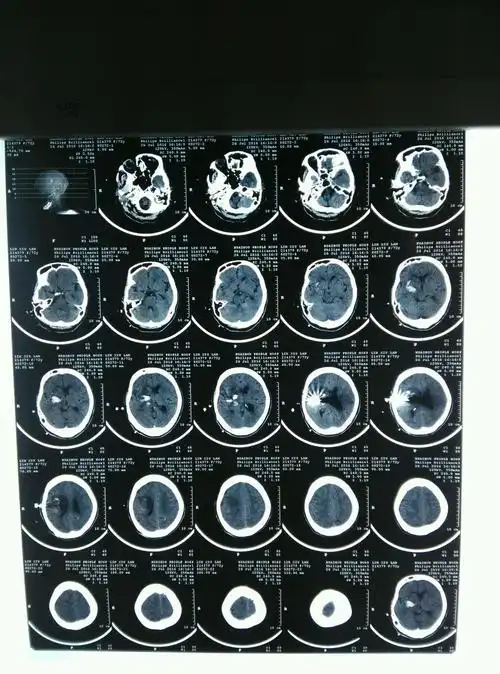

脑出血 有两次ct片子,第一次是5月6号的(出血明显) 第二次是5月14号的